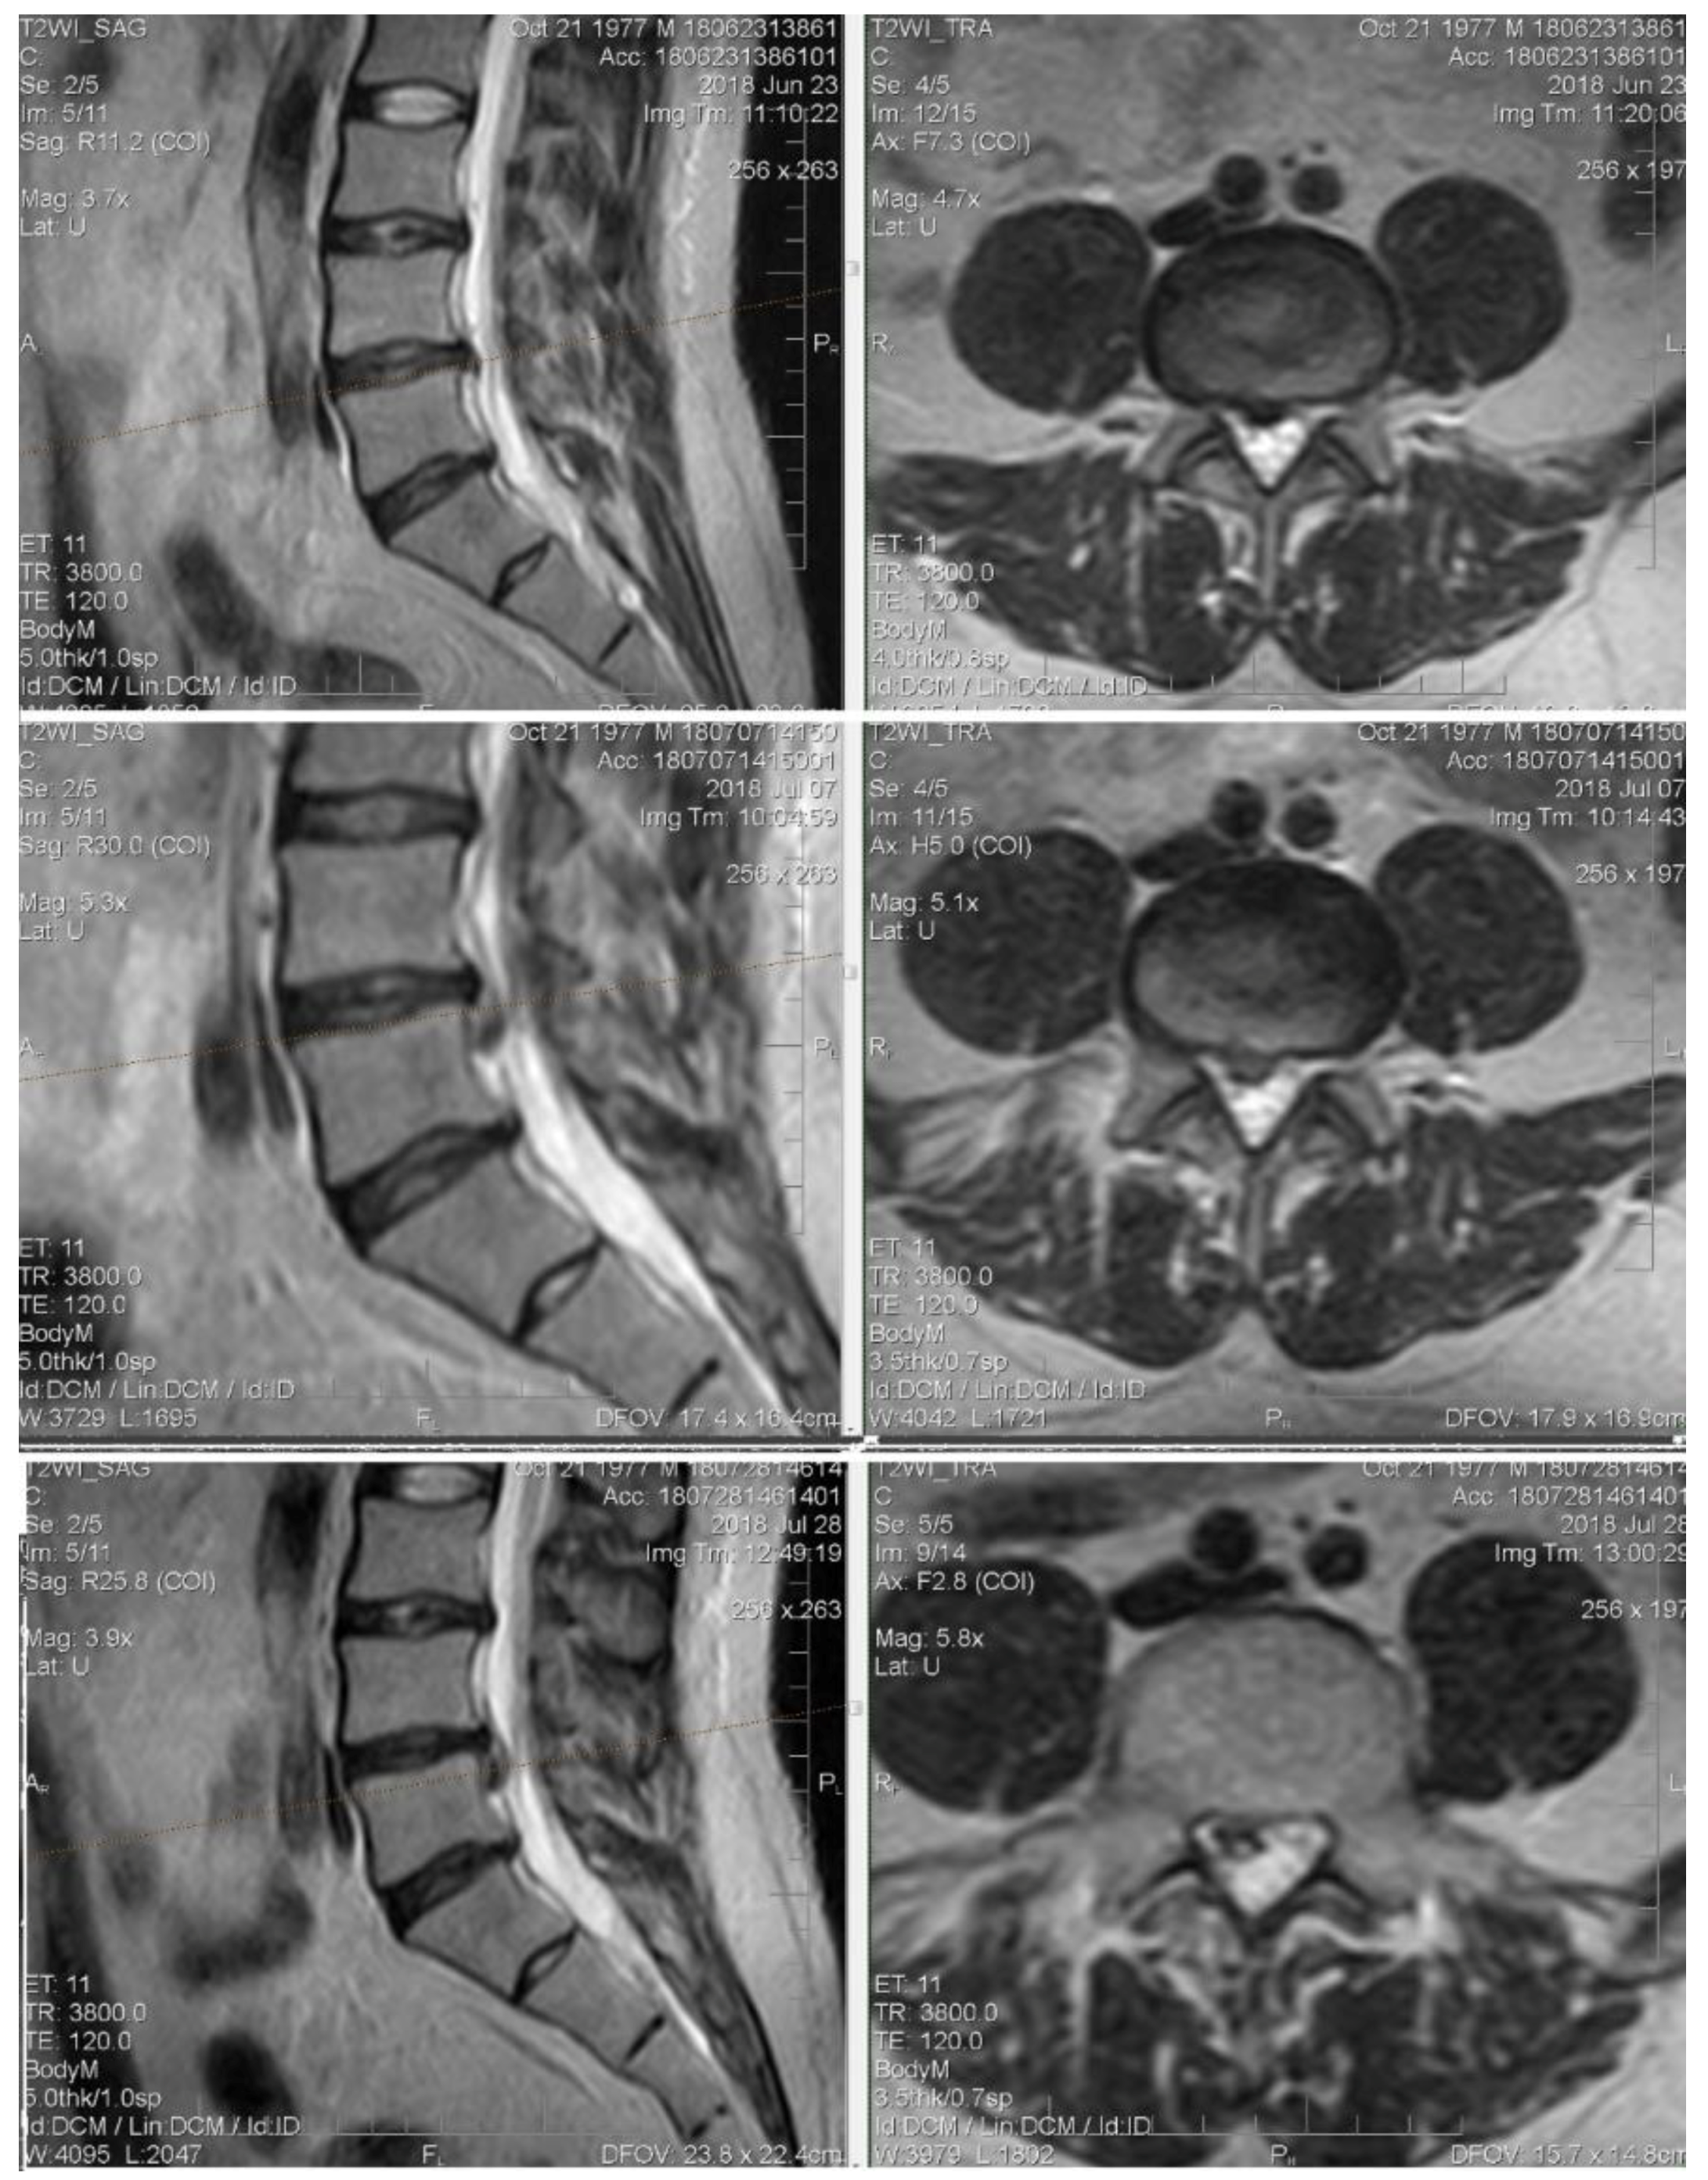

4.3. Clinical Case 2 (L-Aesineate 5 mL Group)

In our opinion, this case needs an additional comment. It is generally considered that an increase in the size of the intervertebral disk hernia is a negative predictor, but the data from numerous publications and observations indicate the opposite. Intervertebral hernia accompanied by sequestration or extrusion, without motor deficiency clinically, is more likely to by reabsorbed and “shrink”. Despite the large size, it is easier to dehydrate and reconfigure them in such a way that they do not create compressions of neuronal structures [59,60].

Patient M., 41, complains of moderate back pain and “striking” pain in the right leg. At the primary examination: excess body weight, neurological status without sensory, reflex, or motor deficiency. VAS: 5 points. Straight leg test right-side to 35°.

MRI: On the background of degenerative-degenerative changes and protrusions, there is a L4–L5 level hernia. At the first control, extrusion of bulging and caudal migration.

It is interesting that the VAS values at the first control was 0 points. In this case, the increase in size and shape changes were an element of sanogenesis: caudally displaced hernia does not compress neuronal structures (Figure 7).

Figure 7. Initial T2-weighted MRI of the lumbar spine shows a large extruded disc at the L4-L5 level and the follow-up imaging shows up migrating fragment.